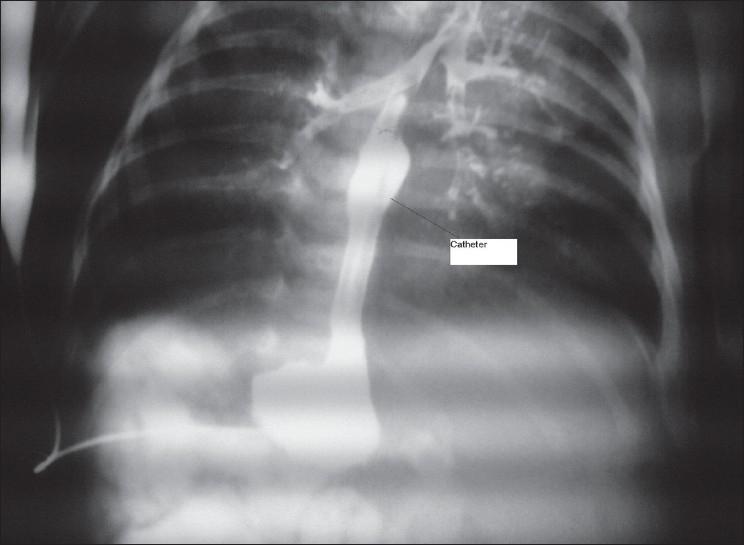

Esophageal Atresia: Migration of the gastrostomy tube into the bronchus.

A 2-day-old baby boy, 38 weeks gestation, weight 2000 g was brought due to hypersalivation and imperforate anus with gasless abdomen on plain X-ray. He underwent a gastrostomy tube insertion and colostomy. In contrast study of the stomach, on the 5th postoperative day, the dye spilled into the tracheo bronchial tree and the catheter was seen, entering the right main bronchus. The patient underwent right thoracotomy and the presence of fistula and catheter were confirmed. The fistula and distal esophagus were closed and fixed to the prevertebral fascia because of a long gap. He is under follow-up and recieving home care for a later delayed primary anastomosis.